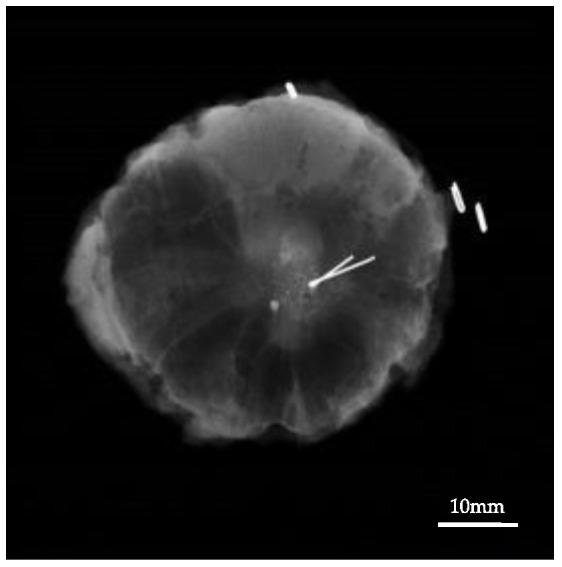

Accurate pre-operative localization of nonpalpable lesions plays a pivotal role in guiding breast-conserving surgery (BCS). In this multicenter feasibility study, nonpalpable breast lesions were localized using a handheld magnetic probe (TAKUMI) and a magnetic marker (Guiding-Marker System). The magnetic marker was preoperatively placed within the target lesion under ultrasound or stereo-guidance. Additionally, a dye was injected subcutaneously to indicate the extent of the tumor excision. Surgeons checked for the marker within the lesion using a magnetic probe. The magnetic probe could detect the guiding marker and accurately localize the target lesion intraoperatively. All patients with breast cancer underwent wide excision with a safety margin of ≥5 mm. The presence of the guiding-marker within the resected specimen was the primary outcome and the pathological margin status and re-excision rate were the secondary outcomes. Eighty-seven patients with nonpalpable lesions who underwent BCS, from January to March of 2019 and from January to July of 2020, were recruited. The magnetic marker was detected in all resected specimens. The surgical margin was positive only in 5/82 (6.1%) patients; these patients underwent re-excision. This feasibility study demonstrated that the magnetic guiding localization system is useful for the detection and excision of nonpalpable breast lesions.